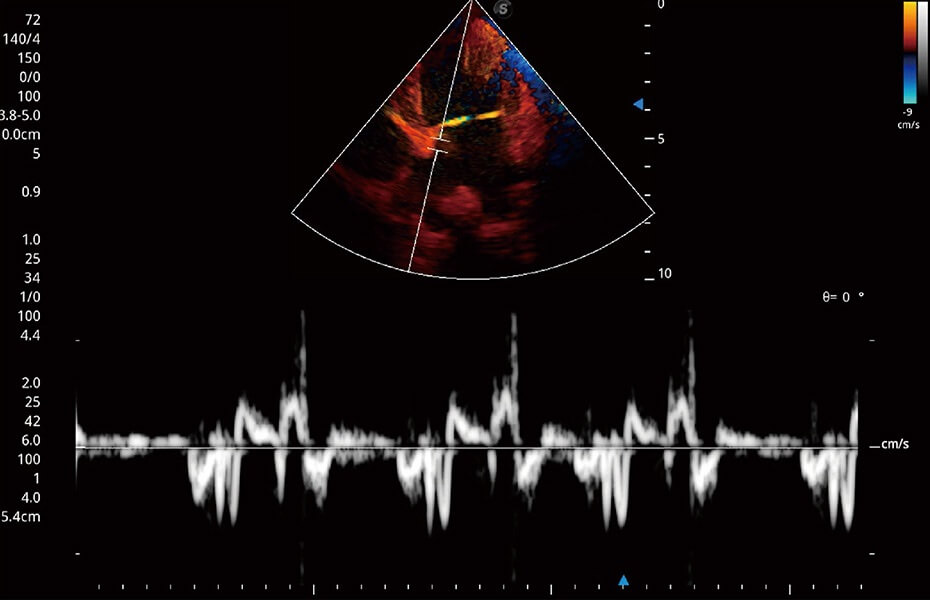

ProPet 60 作为一款高端台式动物超声设备,为动物医生的日常诊断提供了一系列贴合动物临床需求、解决临床实际问题的高级成像功能。凭借全系列高清探头,满足医生对腹部、心脏、生殖、浅表、肌骨等成像的所有需求,切实帮助您提升检查效率,提高诊断信心。